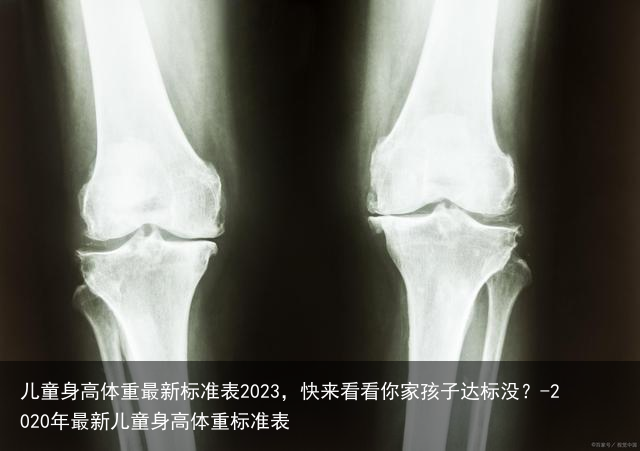

身高的生长主要取决于长骨的生长。

长骨中间的骨干与两侧膨大的骨骺之间有骨骺软骨,常被称为骨垢线。骨骺线闭合,骨骺不再生长。

儿童身高体重最新标准表2023,快来看看你家孩子达标没?-2020年最新儿童身高体重标准表骨骺线闭合,骨骺不再生长